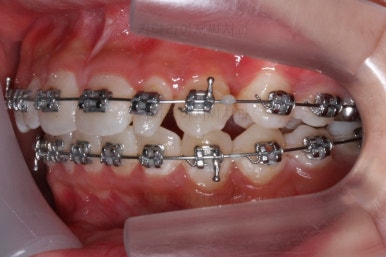

이번에 사용한 장치는 메탈장치였고, 치료 초기에는 매복치를 제대로 꺼내는데 초점을 맞췄어요.

장치를 부착하고 철사를 조절해주면 서서히 나옵니다.

처음 장치를 부착한 이 후 8개월이 흐른 시점이네요. 꽤나 오랫동안 천천히 송곳니를 가지런하게 해줘요.

치료 10개월째의 모습입니다.

이정도면 다 끝난 것 같은 느낌이 드시지 않나요? 과개교합도 개선시켰고 매복치아 덧니도 가지런하게 했어요.

우선 현재 상태에서는 사이즈를 크게 하지 못하기 때문에 왜소치 좌우로 틈새를 만들어주기로 했습니다.

왜소치 좌우로 틈을 일부러 만든 상태입니다.

그 후에 임시 개념으로 사이즈를 크게 만들어 줬어요.

사이즈를 크게 한 뒤에도 약간의 틈이 남아서 다시 틈을 줄여주는 과정을 진행했어요.